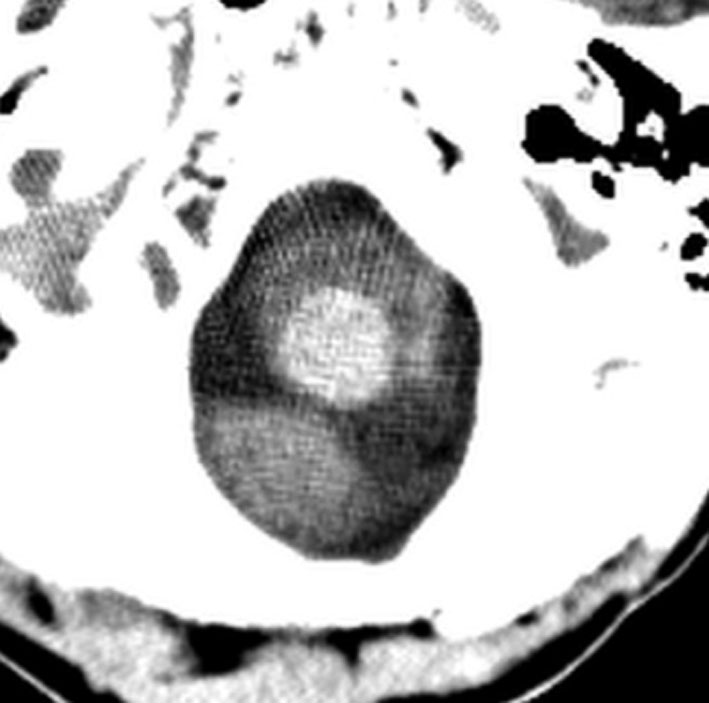

全脳照射後の脳内石灰化(青年期例)

1985年,17才のときに松果体ジャーミノーマで全脳照射45グレイ,18分割,1回2.5グレイの放射線治療を受けました。照射後の数年は普通に社会復帰ができていたということで,大学を卒業し,就職もしていました。しかし,20代後半くらいから認知機能低下(高次脳機能障害)が目立つようになりました。41才で脳幹部梗塞になりましたが,放射線治療が原因の脳血管障害でした。大脳にも小脳にも広範囲に脳内石灰化が散らばっています(白い点状に見えるもの全て)。30代からさらに進行悪化しました。脳の萎縮は目立ちませんが,MRIでは,大脳基底核の多数のラクナ梗塞,多数の海綿状血管腫,中大脳動脈の壁不整と狭窄もみられました。45才で介護施設に入所しています。このような所見は,1日線量2.5グレイを用いていた頃の小児患者さんでみられます。